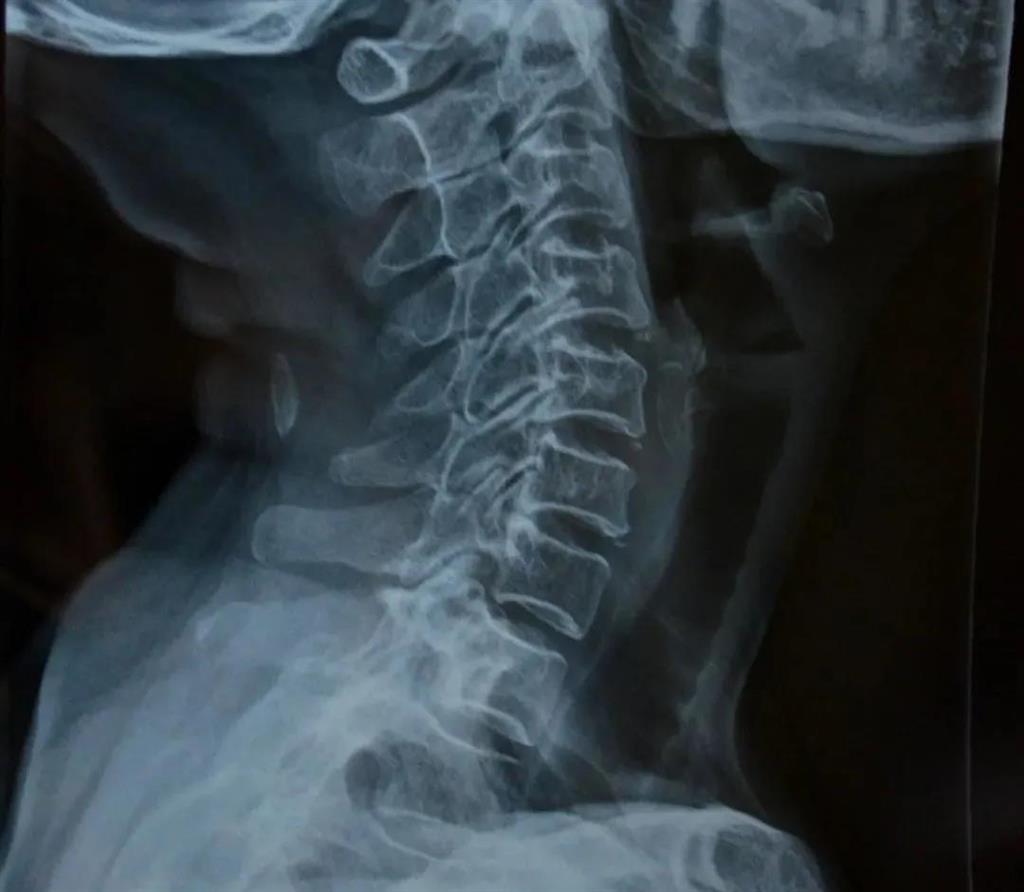

X光片檢查

——圖源網(wǎng)絡

可得信息:

(1)判斷頸椎的大體形態(tài)、曲度、穩(wěn)定性;

(2)判斷骨頭結構是否出現(xiàn)破壞的情況;

(3)是否出現(xiàn)骨質(zhì)增生或先天畸形的情況。